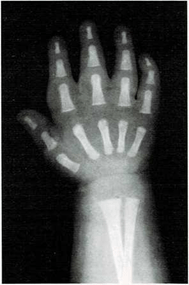

Mi madre me respondió: “Una razón de que lo encuentres blando es que sus huesos no son tan duros como los tuyos. Los niños, al nacer, tienen muy pocos huesos duros. Los huesos de su esqueleto se componen sobre todo de cartílago. Pero las células óseas trabajan sin descanso, y por ello sus huesos crecen y se endurecen muy deprisa. Tus huesos son más largos y duros que los del niño. Los huesos seguirán creciendo y se endurecerán hasta tus veinte años.

Una vez el médico me hizo una radiografía de la muñeca. Quería ver cómo crecían mis huesos. Yo le pregunté cómo era posible que mediante una foto de mis huesos pudiera saber qué le pasaba a mi esqueleto.

El médico me respondió: “Tu muñeca tiene ocho huesos. Pero no todos crecen a la vez. Los huesos de la muñeca de algunos niños crecen más deprisa o más despacio que los de otros niños. Pero los huesos de la muñeca crecen a un mismo ritmo en todos los niños sanos. Si los huesos de tu muñeca salen bien en la radiografía, quiere decir que el resto de los huesos de tu cuerpo también están bien.”

En ella ya se ven claramente los ocho huesos.